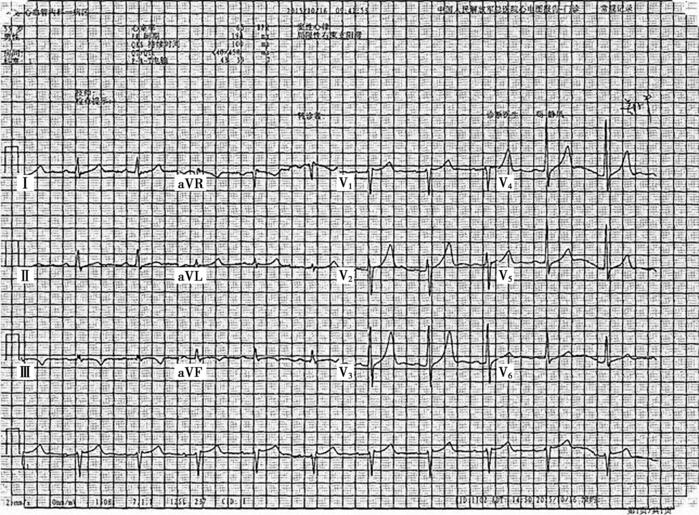

入院心电图:

大致正常心电图(图20-1)。

图20-1 入院心电图